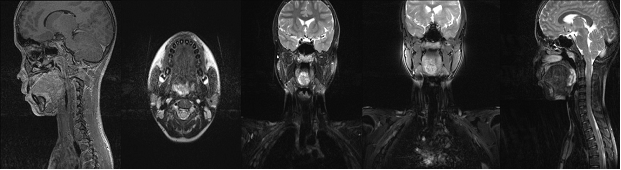

A 14 year old male presented with complaints of dysphagia for one year. On examination, a pinkish irregular growth approximately 3.5cm in transverse diameter was seen in right side of base of tongue. It was immobile, nontender, firm, and non compressible swelling which was blanching on pressure. Rest of the ENT examination was normal. A MRI scan was done and suggestive of mass epicentered in posterior 1/3 of tongue mainly on right side, crossing mid line with size of 20 X 29 X 34mm and infiltrating the intrinsic muscles of the tongue. It was heterogeneously hypointense on T1W1 and heterogeneously hyperintense in T2W1 images. Delayed post contrast enhancement was noted and provisional diagnosis of Haemangiolymphangioma was given. The patient was given empirical treatment with oral propanolol and local sclerosant (phenol) injection. However, there was no decrease in size of the mass and decision was taken for surgical excision. The patient was taken up for coblation assisted surgery under general anaesthesia. The upfront tracheostomy was offered to secure the airway and to avoid any postoperative complications after obtaining informed consent.

Figure 7 MRI.

The neurofibroma can be differentiated from Schwannomas, which are capsulated tumour, showing Antony A & B pattern along with verocay bodies. Other differential diagnosis can be lymphangioma, haemangioma, haemartoma, nerve sheath myxoma and dermoid cyst.6,10  MR imaging is currently modality of choice for these lesions. On MRI these are seen as low to intermediate signal intensity on T1-weighted images and high signal intensity on T2-weighted images. The signal intensity on T2-weighted images may be either homogeneously hyperintense. Target sign may be present. Neurofibroma and Schwannoma appear similar in MRI, except nerve can be identified in Schwannoma and more often shows degenerative changes.2 Treatment of choice for peripheral nerve sheath tumour is surgical excision. Upfront precautionary tracheostomy in large lesions at the base of tongue region is advisable. The extreme vascularity with poor cleavage plane of the lesion and a possibility of an aberrant vessel in the neck should be kept in mind while attempting excision. 5,7,8,10 The surgical excision can be assisted with laser, electrocautery, harmonic scalpel or coblation depending on the surgeon`s preference. In this case we found coblation was very useful in tumor handling at base of tongue region and the hemostasis during procedure was excellent. The postoperative swelling was less than expected and there was a minimal pain and a quick recovery.